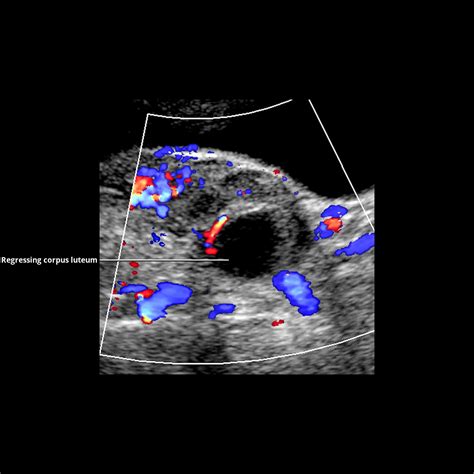

But here’s the crucial part: while the egg originated in the ovary and was released by it, and the initial fertilization might happen near it, the zygote does not develop into a baby within the ovary itself . Instead, after fertilization, this tiny zygote begins a rapid series of cell divisions, transforming into a multicellular structure known as a morula , and then a blastocyst . All this cellular transformation happens while the blastocyst is still making its way down the fallopian tube towards the uterus. This entire process, from ovulation to the arrival of the blastocyst in the uterus, usually takes about 3-5 days. During this time, the ovary continues its work, particularly the part of the follicle that released the egg, which transforms into something called the corpus luteum . The corpus luteum is a temporary endocrine gland that produces a significant amount of progesterone . This progesterone is absolutely vital because it helps thicken and enrich the uterine lining, creating a welcoming, nutrient-rich environment for the blastocyst to implant. Without this progesterone from the corpus luteum, successful implantation would be incredibly difficult, if not impossible. So, while the actual development of the baby’s organs and systems won’t occur in the ovary, the ovary’s initial actions – releasing the egg and then providing the hormonal support via the corpus luteum – are indispensable for setting the stage for pregnancy. It’s an intricate dance, and the ovary is definitely leading the opening number!

Why is this progesterone so important? It’s essentially the linchpin that maintains the pregnancy in its nascent stages. Progesterone helps to thicken and prepare the uterine lining (the endometrium) for implantation, and once implantation occurs, it prevents the uterine muscles from contracting prematurely, which could otherwise lead to a miscarriage. It also supports the development of the placenta and helps to suppress the mother’s immune response, ensuring that her body doesn’t reject the developing embryo. Without adequate progesterone levels from the ovarian corpus luteum , the pregnancy simply cannot be sustained. In some cases, if a woman’s body doesn’t produce enough progesterone, supplementary progesterone might be prescribed to support the early pregnancy. Around weeks 7-10 of gestation, something incredible happens: the placenta , which has been developing rapidly within the uterus, takes over the primary production of progesterone. At this point, the corpus luteum in the ovary typically starts to degenerate , having successfully passed the baton to the new, fully-formed placental structure. This transition is a critical milestone in pregnancy, marking a shift in hormonal command. While the ovaries’ direct hormonal contribution might lessen after the first trimester, they continue to produce other important hormones, albeit in smaller quantities, and remain integral to the overall endocrine system. Their long-term health is also important for the overall hormonal balance that impacts a woman’s body throughout her life. So, while the baby isn’t developing in the ovary, the ovary’s early hormonal output is absolutely indispensable for creating and sustaining the very environment where that development can successfully unfold. It’s a fantastic example of the interconnectedness of our body’s systems, all working together for the ultimate goal of creating and nourishing new life. The ovaries truly set the stage for success!